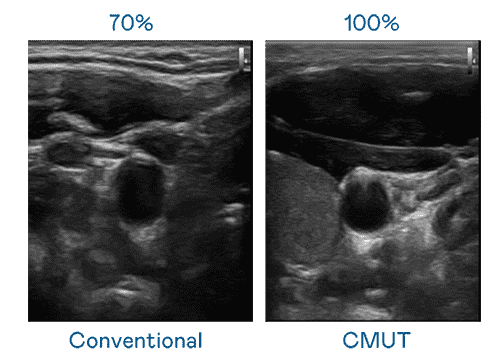

CMUT 技术是一种用电容式微机电元件来产生超音波讯号的技术。。与传统 PZT 压电式技术相比,,CMUT 频宽增加 30%,,,更宽频的超音波讯号让影像解析度大幅提升,,是实现高影像品质医疗超音波扫描、、、促进精准医疗发展的关键技术。。

大频宽带来超清晰影像

超音波影像的解析度高低,,,首先取决于探头能发出的讯号频宽。。。。财神娱乐 CMUT 可提供高清晰的超音波讯号,,提供高频宽、、高灵敏度、、影像纹理细节更高的超音波影像,,,协助医护人员缩短影像判读时间及利用精准的医疗影像进行诊断。。。